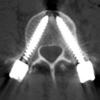

Wirbelsäulenoperationen

Wenn die Degeneration an der Wirbelsäule fortgeschritten ist, dann kann man häufig mit „kleinen Maßnahmen“ oft nicht auf Dauer helfen. Schmerzen können sich zwar trotzdem kurzzeitig bessern. Das Problem bleibt jedoch chronisch und kehrt wieder. Soll die Entstehungsursache von Rücken und/oder Beinschmerzen im fortgeschrittenen Stadium beseitigt werden, dann helfen häufig nur offene Wirbelsäulenoperationen. Auch diese Eingriffe werden in mikrochirurgischer Technik und aller Sorgfalt möglichst minimalinavasiv durchgeführt. Jedoch hinterlassen sie Narben und der Patient bedarf häufig einer längeren Erholungsphase und eines komplexes krankengymnastischen Rahmenprogramms. Leider ist dann auch nicht immer die vollständige Schmerzbeseitigung möglich. Das Ziel ist eine deutliche Schmerzreduktion und eine Verminderung des Schmerzmedikamentenbedarfs.